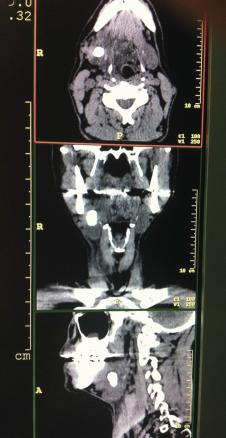

L’examen biologique est normal : absence de syndrome inflammatoire, hémogramme sans anomalie. La tomodensitométrie cervicale (fig. 2 et 3 ) montre une volumineuse formation calcifiée (20 × 15 mm). Cette masse correspond à la glande salivaire sous-mandibulaire droite totalement calcifiée, sans caractéristiques péjoratives.

L’examen biologique est normal : absence de syndrome inflammatoire, hémogramme sans anomalie. La tomodensitométrie cervicale (